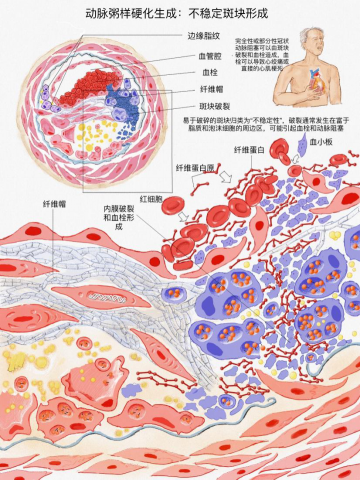

我院成功举办2020年首届大学生医学形态学绘图大赛

为丰富新冠疫情期间的文化生活,深化同学们对机体结构的认识及艺术鉴赏,展示大体及微观结构之精髓。近期,由我校教务处和成人卡通

主办、形态学实验中心承办的首届“大学生医学形态学绘图大赛” 顺利完成。此次大赛的作品主要来自我校17-19级医学类专业。评委根据对参赛作品的科学性、艺术性、创新性和应用性等方面进行综合评审,共评出12幅作品分别获得一、二、三等奖。

附件1:2020年首届大学生医学形态学绘图大赛获奖名单